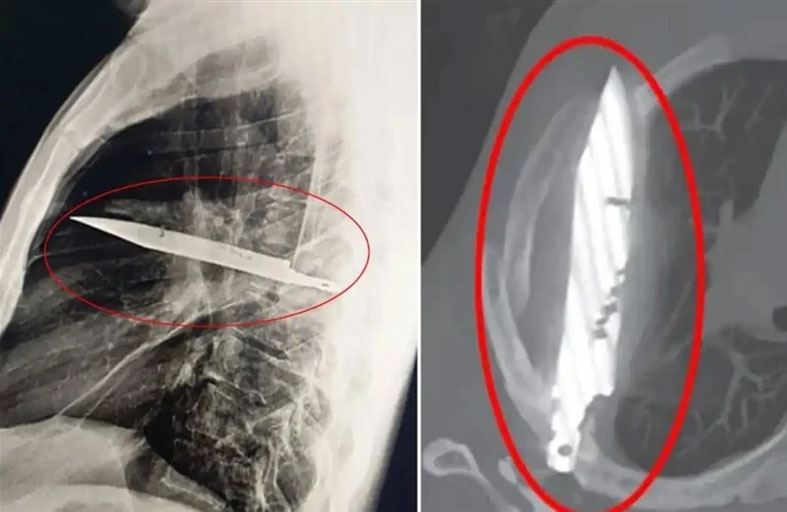

العثور على سكين مستقرة في صدر رجل 8 أعوام

في واقعة طبية نادرة، عثر أطباء في تنزانيا على سكين ضخم مغروس في صدر رجل مُنذ نحو 8 سنوات، بعد أن توجه إلى المستشفى شاكياً من آلام وإفرازات غريبة بمنطقة الصدر. وقالت التقارير الطبية إن الرجل، البالغ من العمر 44 عاماً، لم يكن يعاني من أي أعراض أخرى لافتة، إذ لم يشكُ من صعوبة في التنفس أو الحمى، كما كانت علاماته الحيوية طبيعية، وفقً لصحيفة "ذا صن" البريطانية. لكن فحوصات الأشعة كشفت عن وجود شيء معدني كبير اخترق جسده عبر لوح كتفه الأيمن، واستقر على مسافة خطيرة من أعضائه الحيوية، دون أن يلحظ طوال هذه السنوات. وبحسب المريض، فقد تعرض لإصابات متعددة في الوجه والظهر والصدر والبطن خلال "مشاجرة عنيفة" قبل نحو عقد، وتلقى حينها علاجاً، لكنه لم يكن يعلم أن السكين بقي عالقاً داخل جسده. وأجرى الجراحون عملية دقيقة لاستخراج السكين وتصريف الصديد الناتج عن تلف الأنسجة، فيما قضى المريض 24 ساعة في العناية المركزة، ثم 10 أيام في الجناح العام، قبل أن يتعافى ويغادر المستشفى بحالة مستقرة.